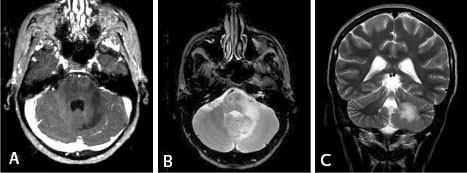

Patient 19 years old, female, with AIDS, and

pathologically proven diagnosis of progressive multifocal

leucoencephalopathy (PML).

Dr. Tampieri